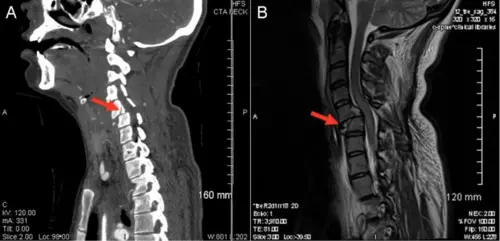

25-year-old female restrained driver was in a rollover MVA and suffered a C5-C6 fracture with spinal cord injury. (Figure 1).

Figure 1. Panel A: computerized tomography (CT) scan of the neck showing C5-C6 fracture and dislocation (arrow). Panel B: Accompanying magnetic resonance imaging (MRI) of the neck. Courtesy: Dr. Schmitz